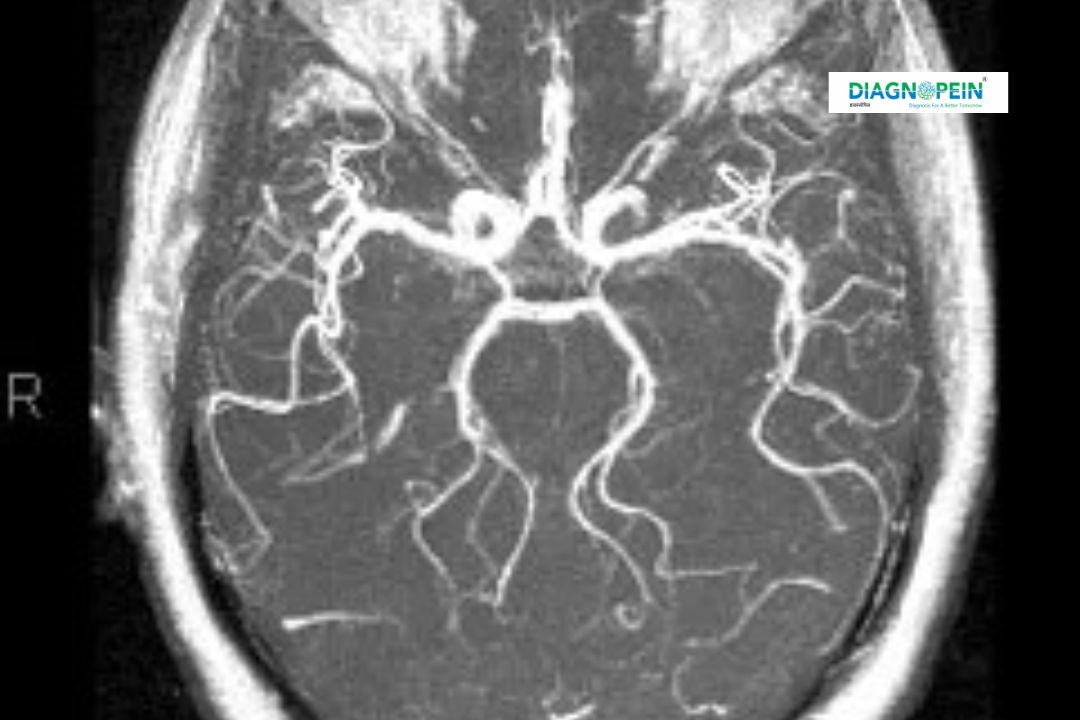

MRI Brain Angio and MRI Neck Angio are non-invasive medical imaging tests that produce high-resolution images of the brain and neck blood vessels. These tests use magnetic resonance imaging (MRI) technology combined with angiography to analyze blood flow and detect abnormalities in veins and arteries.

3. High-quality, 3D visualization of blood vessels for accurate diagnosis.

1. Flow dynamics of major brain and neck arteries.

2. Vessel integrity, stenosis, or occlusion.

3. Presence of aneurysms or vascular malformations.

4. Blood flow symmetry and collateral circulation.